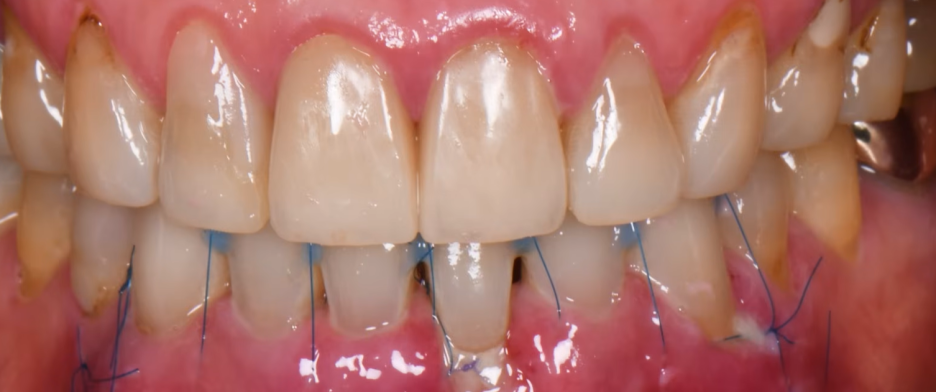

출처 - 권의시선 : 치과의사 권낙현 유튜브  수술후 실로 단단히 고정한 모습

출처 - 권의시선 : 치과의사 권낙현 유튜브